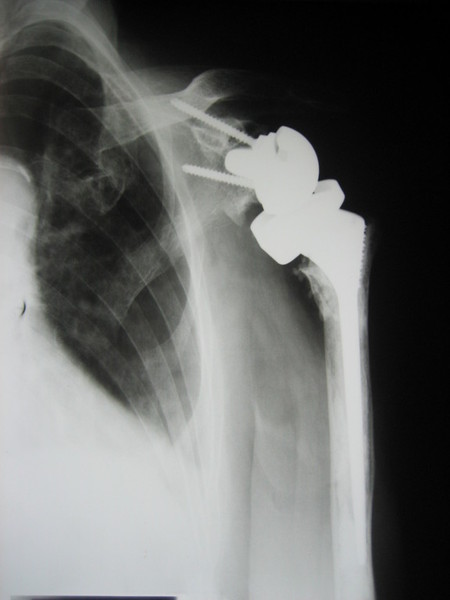

Chirurgia Artroscopica ed Open della Spalla - Chirurgia dell'Anca Chirurgia del Ginocchio - Chirurgia della Mano - Ricostruzione legamentosa - Chirurgia Protesica Articolare Ricostruzione Cartilaginea - Impianto di Staminali Adulte e Fattori di Crescita come Chirurgia Rigenerativa- Estetica Ortopedica Ricostruttiva Chirurgia Nervosa Periferica agli arti-Terapia Infiltrativa.